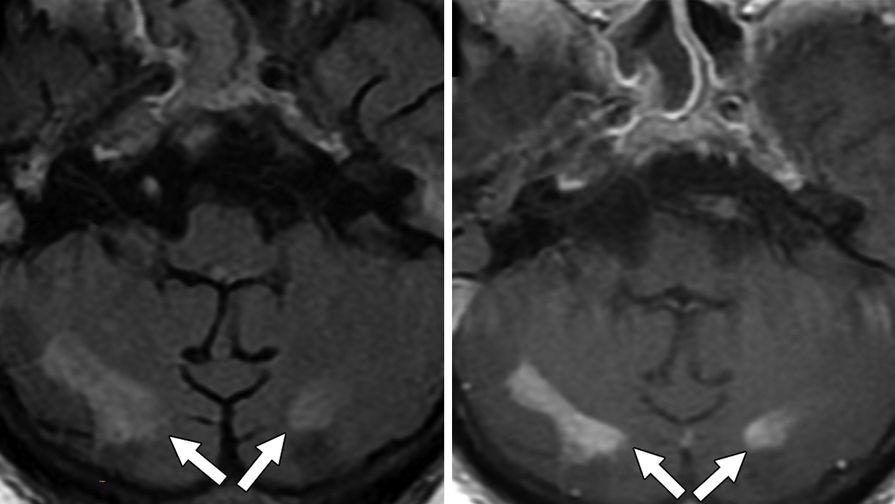

Из 2820 пациентов с COVID-19, с которыми имели дело авторы работы в период с 1 марта по 18 июня 2020 г., 59 прошли МРТ головного мозга. У многих наблюдались признаки поражения мозга, вызванные рассеянным склерозом, инсультами, нехваткой кислорода в крови, недостаточным кровоснабжением мозга и прочими факторами. Но также исследователи заметили, что у шести пациентов (10,2%) имелись признаки лейкоэнцефалопатии.

«Мы наблюдали обширное слияние очагов поражения белого вещества (с характеристиками и расположением, нетипичными для других причин), микрогеморрагическим кровоизлиянием, с ограниченной диффузией, — пишут исследователи.